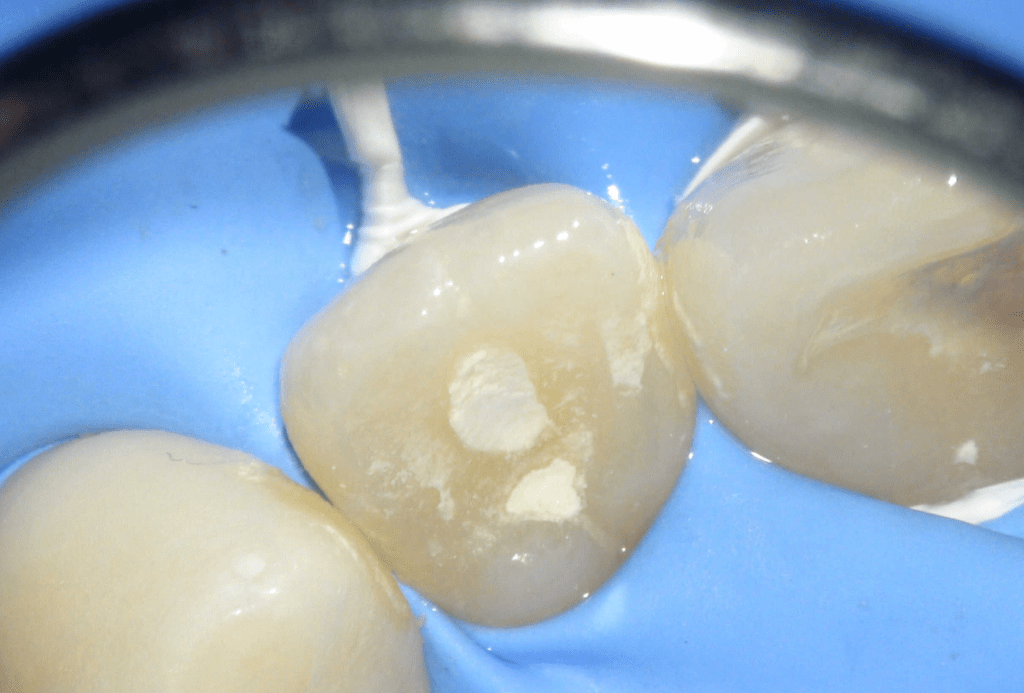

Acceso ultraconservador a través de incrustación reciente